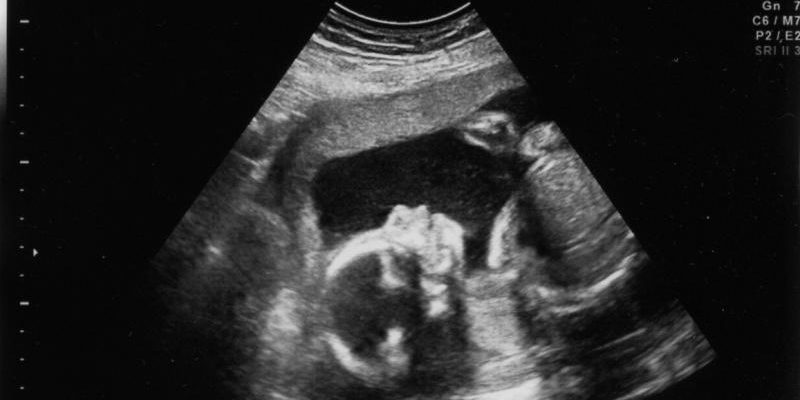

Ова се многу важни информации за докторот за да може да даде каква било препорака или совет при водење на бременоста. Станува збор за брзи, едноставни и високо-специфични тестови, кои во голем процент ги идентификуваат бремените жени кои имаат зголемен ризик да донесат на свет плод со аномалии и дефекти. Проценката за евентуалниот ризик се прави помеѓу 10-13 гестациска недела, но може да се направи и до 22-та недела од бременоста. Тестот се прави со едноствно земање крв од вена и рутински ехо-преглед кај гинекологот.

Софтверот Приска опфаќа мерење на одредени маркери, кои циркулираат во крвта на мајката и се во директна врска со развојот на плодот. Резултатите, се комбинираат со други параметри како возраста и здравствената состојба на пациентката, како и мерките на плодот направени со ултразвук. По компјутерската пресметка на податоците со софтверската програма се добива крајниот резултат, кој укажува колкав е ризикот плодот да има една од следните аномалии: Даунов синдром, Едвардсов синдром, Патау синдром и дефект на затворање на неврална цевка.